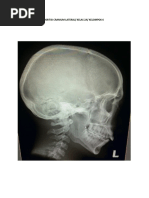

LATERAL VIEW

Tampak lateral Sella Tursica

Indentitas: Tidak tercantum identitas pada radiograf

Marker : Tidak tercantum marker

Batas Atas : verteks

Batas Bawah: Maxilla

Proyeksi: Seluruh bagian anatomi yang dibutuhkan

tidAk terpotong

Faktor Eksposi: faktor eksposi sudah optimal karena

menampilkan perbedaan antara soft tissue dan

trabekula serta batas – batas tulang (margin) tampak

jelas.

Anatomi Radiologi yang Tampak:

1. Anterior Clinoids

2. Posterior Clinoids

3. Dorum Sellae

4. Hypophysis (Pituitary)

5. Sphenoid Sinus